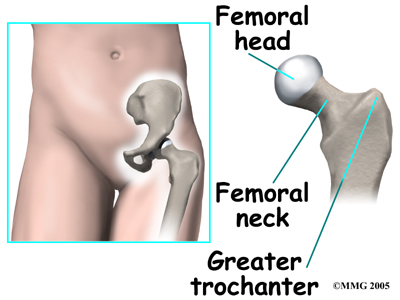

The hip joint is where the thighbone (femur) connects to the pelvis. The joint is made up of two parts. The upper end of the femur is shaped like a ball. It is called the femoral head. The femoral head fits into a socket in the pelvis called the acetabulum. This ball and socket joint is what allows us to move our leg in many directions in relation to our body.

In the growing child, there are special structures at the end of most bones called growth plates. The growth plate is sandwiched between two special areas of the bone called the epiphysis and the metaphysis. The growth plate is made of a special type of cartilage that builds bone on top of the end of the metaphysis and lengthens the bone as we grow. In the hip joint, the femoral head is one of the epiphyses of the femur.

The capital femoral epiphysis is somewhat unique. It is one of the few epiphyses in the body that is inside the joint capsule. (The joint capsule is the tissue that surrounds the joint.) The blood vessels that go to the epiphysis run along the side of the femoral neck and are in danger of being torn or pinched off if something happens to the growth plate. This can result in a loss of the blood supply to the epiphysis.